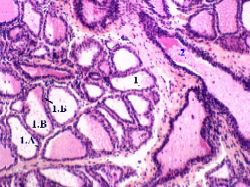

Препарат 53.

Лактирующая молочная железа.  Окраска гематоксилин-эозином.

а) Малое увеличение

Б. Концевые отделы: основные компоненты

1. В лактирующей железе концевые отделы включают два компонента:

альвеолы (1) - полые мешочки, заполненные секретом, и

отходящие от них млечные альвеолярные ходы (2).